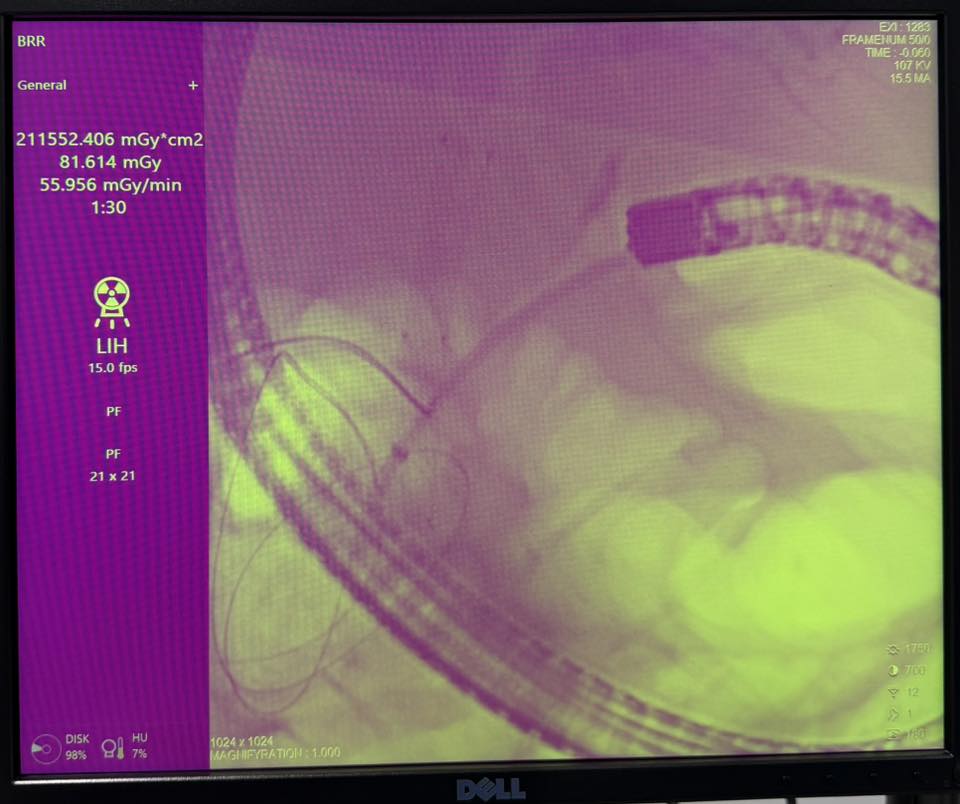

Ҳамин тавр, ба бемор амалиёти ҷарроҳӣ бо истифода аз холангиопанкреатографияи ретроградии эндоскопӣ (ERCP) ва папиллосфинктеротомияи эндоскопӣ бо гузоштани стенти худкушодаи металлии нитинол, ки дарозии 8 см ва диаметри 1 см дорад, ба роҳҳои сафро гузаронида шуд.

Аз сабаби стенози шадиди пайванди меъда ва дувоздаҳангушта, ба бемор иловатан стенти худкушодаи металлии нитинол бо дарозии 12 см ва диаметри 22 мм низ гузошта шуд.